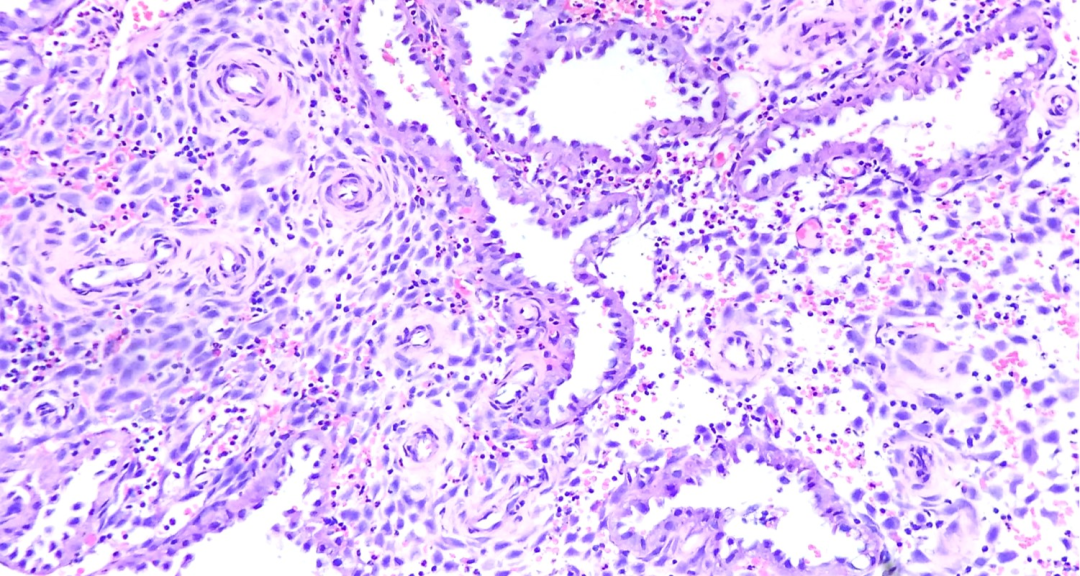

分泌中期 排卵后6-8天

分泌中-晚期

完全盘绕的分泌性腺体,内衬圆形细胞,常呈空泡状的细胞核。这种细胞的胞浆不含大的胞浆空泡,但腺腔内可能出现分泌物。间质尚未开始前蜕膜化。缺乏广泛的空泡和前蜕膜(标志)